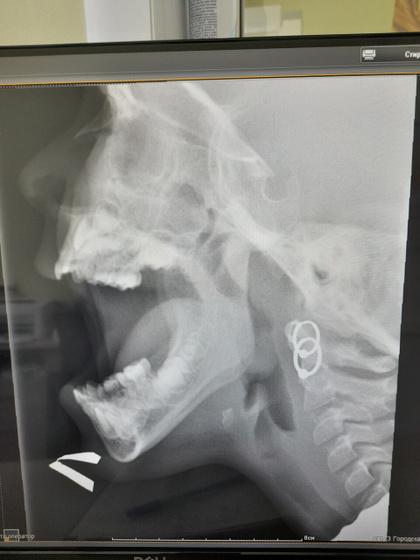

С 2х лет обнаружили аденоиды 2 степени сейчас нам 4 в платных по камере смотрят и отправляют на удаление а в нашей поликлинике лор настаивает на том чтоб тянули как можно дольше.кто нибудь делал операцию в Барнауле 7 больнице.сегодня туда позвонила нас поставили в очередь но сказали совершенно здоровому ребёнку сделать рентген и по нему уже ориентироваться ехать на операцию или нет.дело такое в декабре сделали снимок и нам сказали что аденоиды в норме но наш педиатр настаивала на эндоскопе мы сходили и там сказали надо удалять.барнаул говорит что надо удостовериться точнее и эндоскоп увеличивает вид аденоидов.и им нужен именно снимок.жалобы только на затяжные насморки как в сад пошли так и ходим 1 2 неделю потом месяц сопли лечим.на снимке вроде просвет есть но не понятно норма это или нет.по протоколу этого снимка написали норма.а лор с платной смотрел этот снимок и сказал это не норма далеко